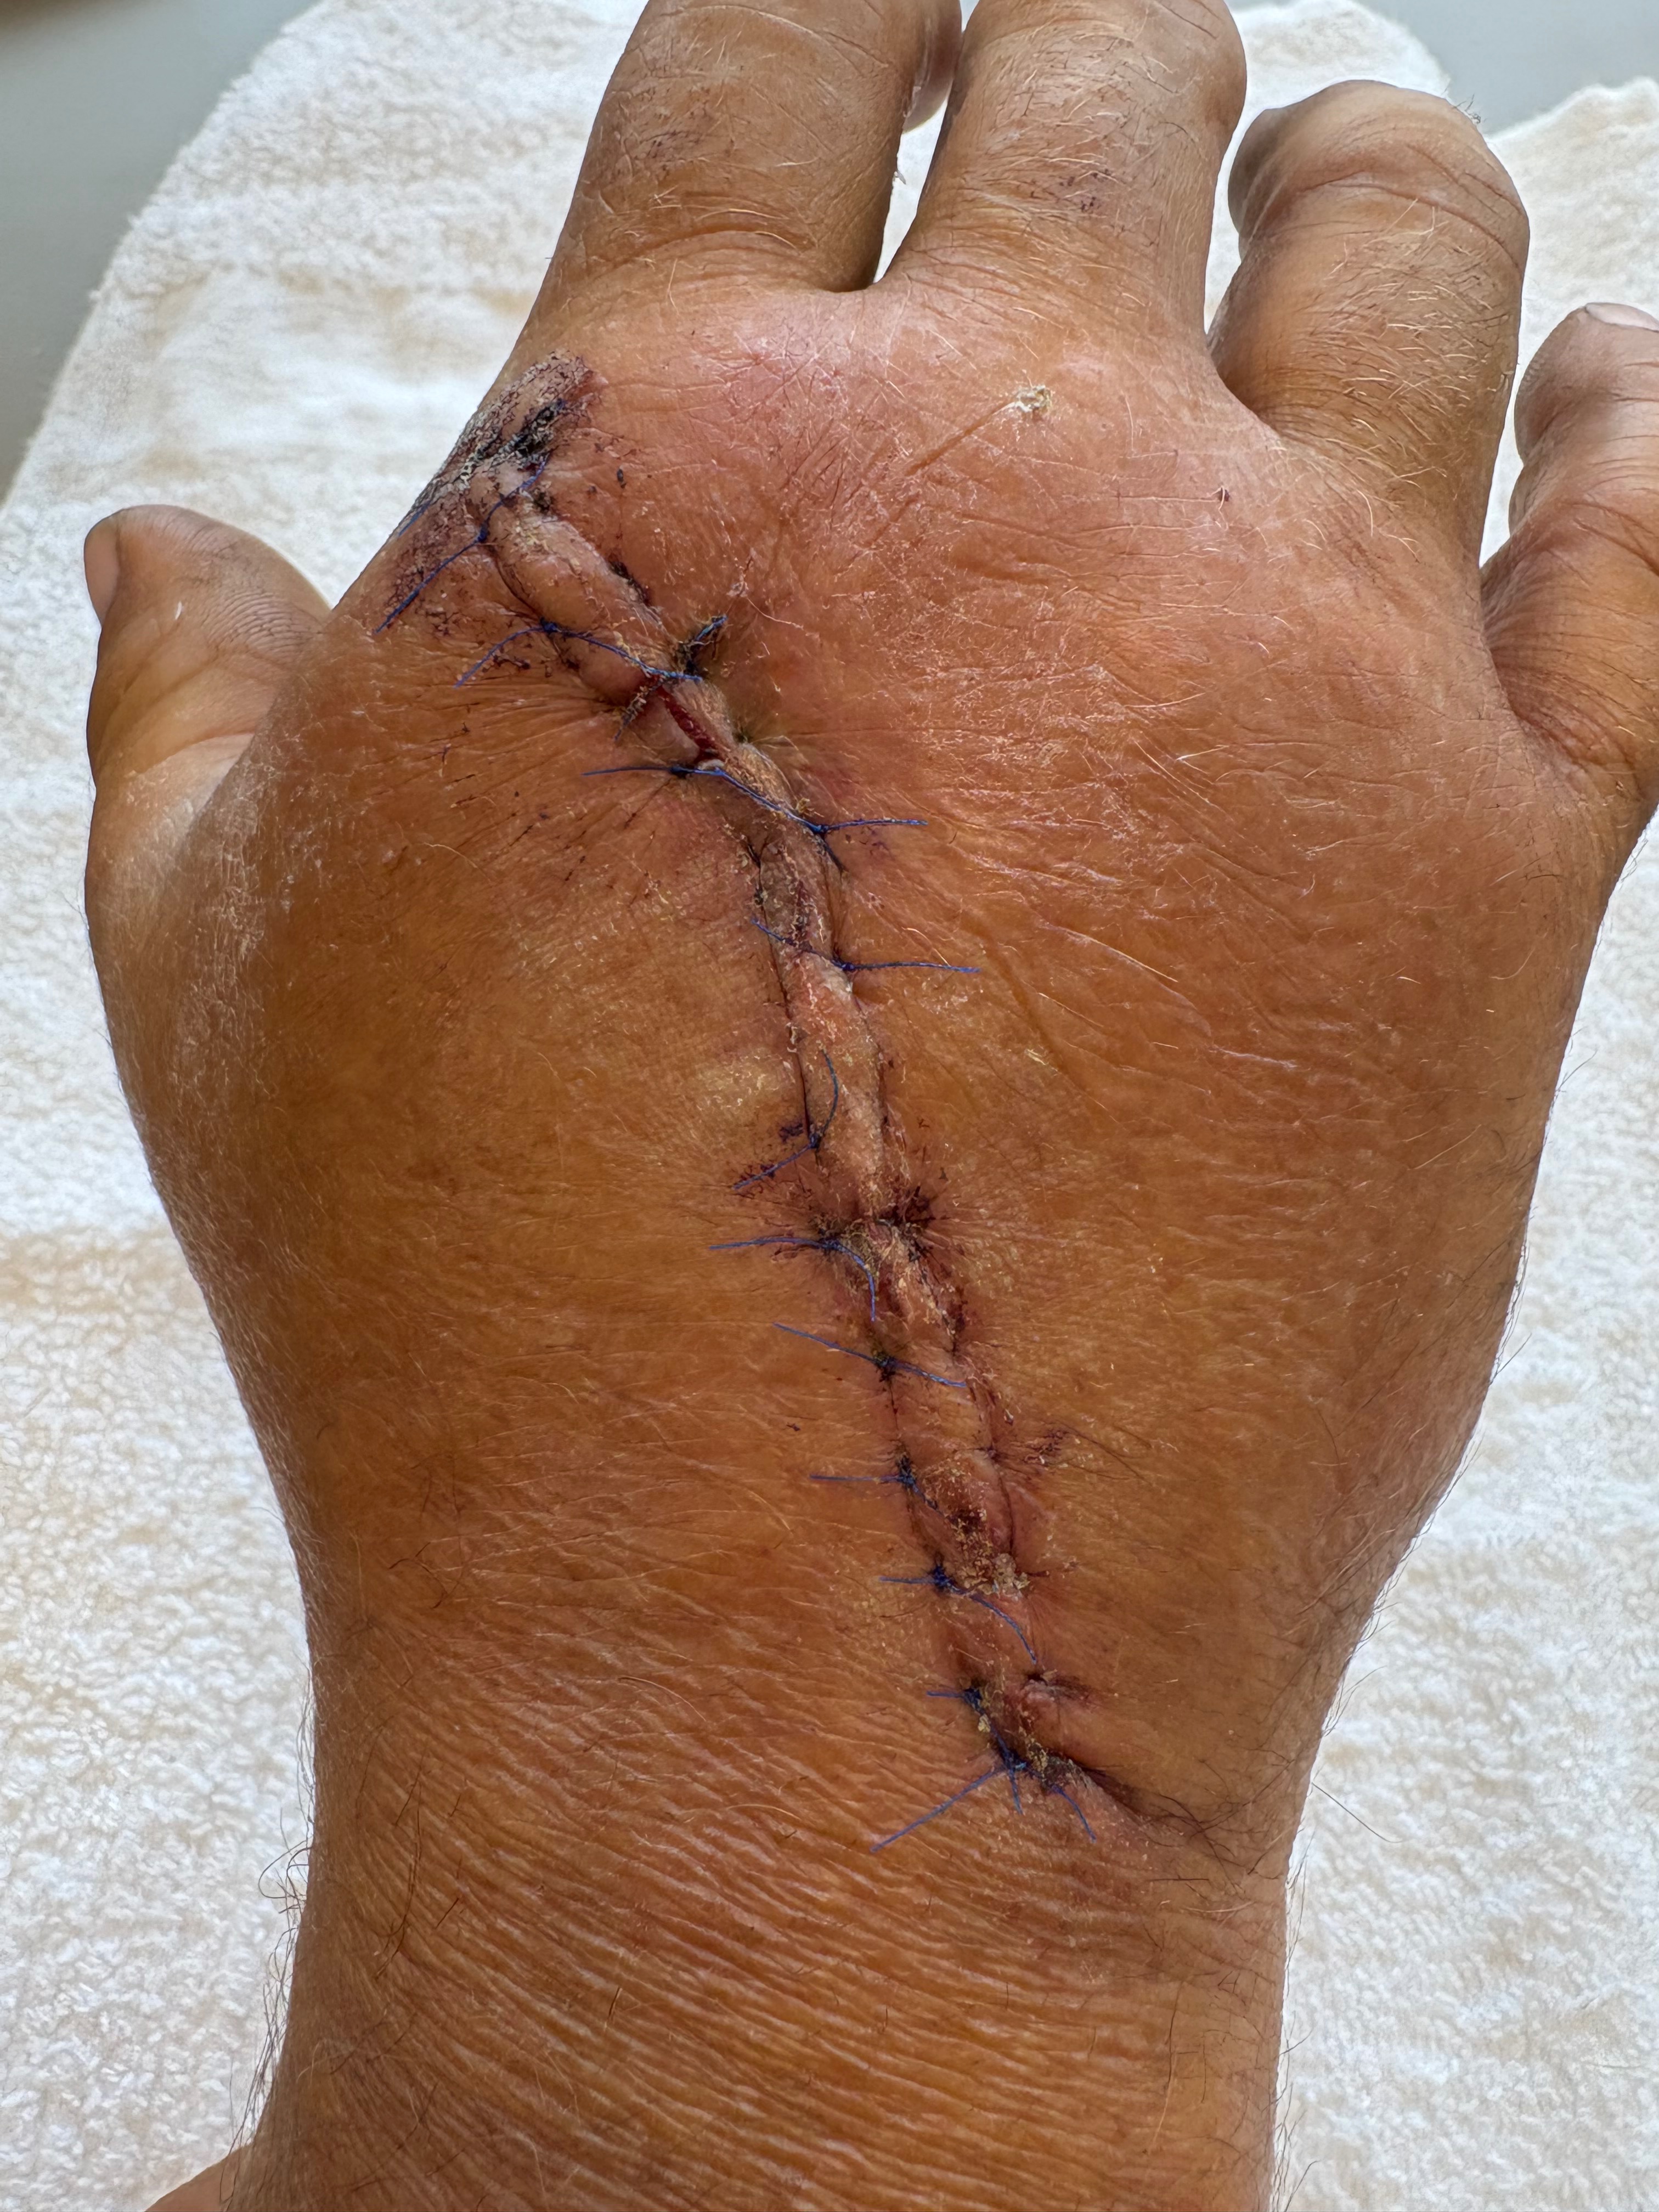

He ended up having basically an emergency surgery that night which went into the next day. He was in surgery for about 2-2 1/2 hours. He now has plates and screws in his hand. Two bones in the top of his hand were affected:

UPDATE: 10/17/25 We are still plugging along here in the Berger house. Chuck is still doing his therapy 2x a week and goes back to see his surgeon in November. The therapist has been trying to get Chuck in to see the doctor earlier than that tho as she is quite concerned about his hand. There is still significant swelling and his index finger still doesn’t bend at the first knuckle (the one at the hand). And his knuckle to his index finger and middle finger are numb. There may also be nerve damage to his thumb. We have also noticed some discoloration to his hand, which even the therapist said isn’t normal.

UPDATE: 10/07/25 Chuck has been going thru therapy 2x a week for his hand injury. Today the therapist told him she is going to talk with the surgeon because she is worried about his index finger. He can’t bend it at the knuckle to his hand. There is a screw head that can be felt thru his skin at that knuckle and the therapist has a feeling he may need to have surgery again to fix that . I seriously hope that’s not the case. Please send many prayers for a speedy recovery for him. This not being able to work is really taking its toll on him.